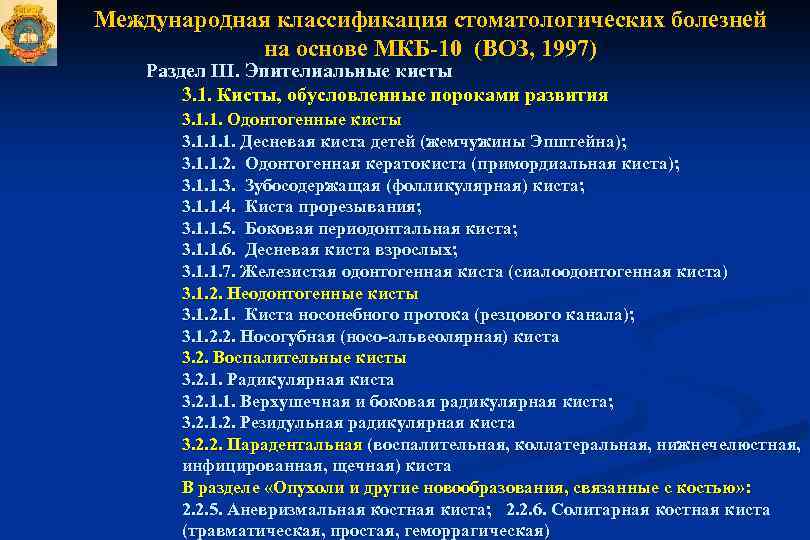

Код мкб 10 атерома головы

Код мкб 10 атерома головы 109 фото